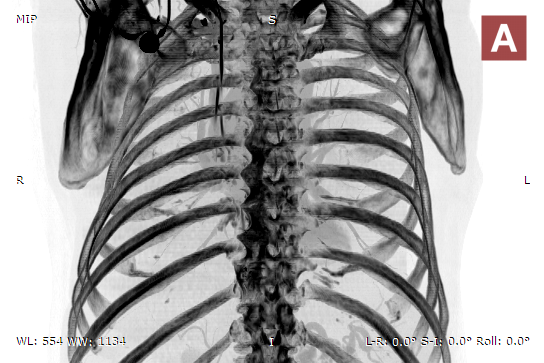

MIP B/W

MIP B/W Inverse